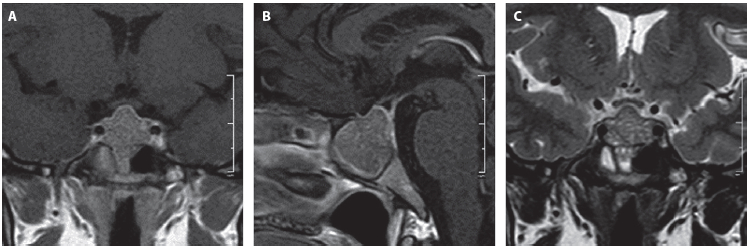

Ante la evidencia de compresión quiasmática y el riesgo de compromiso visual se planteó como primera opción el manejo quirúrgico, que no fue aceptado por la paciente. Se optó como alternativa de manejo una prueba terapéutica con cabergolina en dosis de 0,5 mg semanales con buena tolerancia. Después de 6 meses de tratamiento se realizó una IRM, en la que se evidenció la reducción del volumen tumoral del 73 % sin contacto con el quiasma (Figura 2).

Figura 2. Resonancia de hipófisis posterior al manejo. A. Secuencia T1 contrastada, corte coronal. B. Secuencia T1 contrastada, corte sagital. C. Secuencia T2, corte coronal. Tamaño tumoral residual con diámetros: 16 mm anteroposterior x 13 longitudinal x 17 transverso; volumen de 1,7 mL.